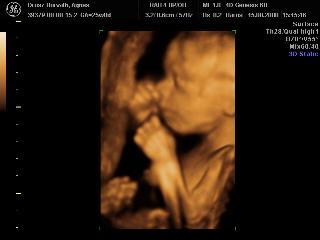

Pannaanya: tök jók a 4D-s képek! Siófok-Sóstó? Na az tőlünk kb. 7 km, ha olvasod és van kedved, akár össze is futhatnánk